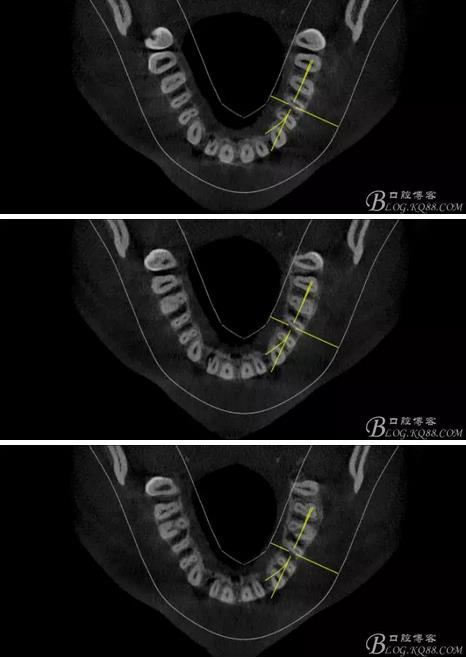

(1) 檢查:12唇側(cè)牙齦可見竇道,牙體顏色較鄰牙暗,無光澤,形態(tài)完整無缺損,唇側(cè)及近遠中向未提及牙周袋。腭側(cè)齦緣輕度紅腫,舌側(cè)窩可探及裂溝,可見浸墨狀痕跡,沿裂溝舌側(cè)探診牙周袋深大于11mm,除患牙外全口牙周狀況良好,為探及牙周袋,牙齦色粉紅。邊緣菲薄,質(zhì)地堅韌。12冷熱診無反應(yīng),叩診(+-),無明顯松動,無咬合創(chuàng)傷。12根尖x線片示,根管中三分之一中可見一斜向線樣透射影像根尖區(qū)及遠中根三分之一可見低密度透射暗影,錐形束CT示12根尖區(qū)唇腭向骨吸收已穿通,根面溝達根中三分之一卷曲分出另一牙根,再未見其他明顯的根管系統(tǒng)。